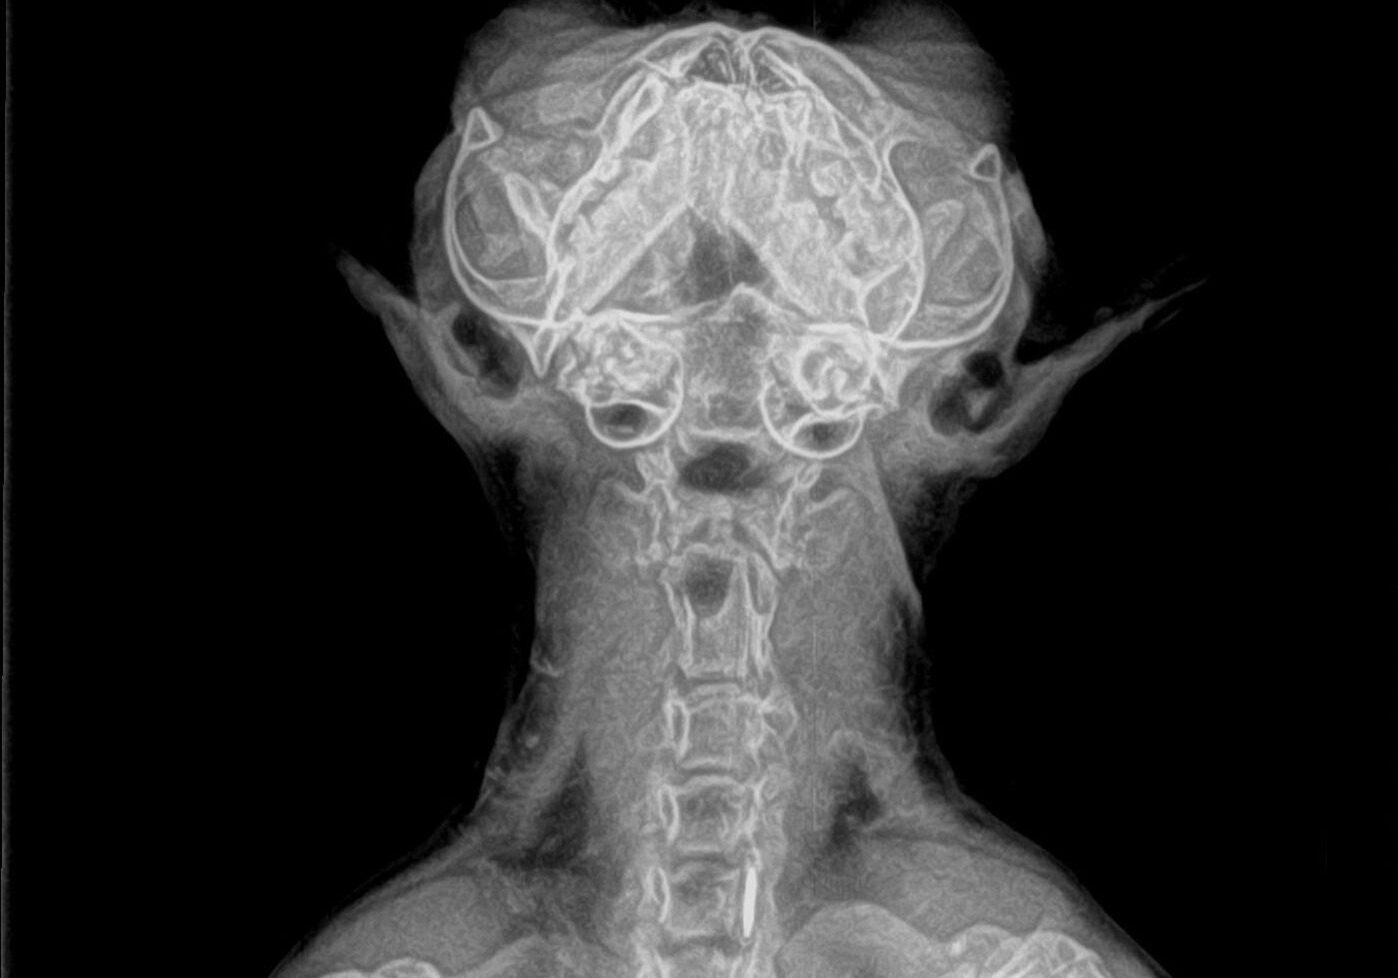

dog x-ray

Digital X-Rays for Pets in Carmel

Some conditions can’t be identified through lab work alone. That’s why we offer digital radiology (X-rays). This safe, noninvasive imaging tool lets us examine your pet’s bones, joints, chest, and abdominal organs while keeping radiation exposure low.

Digital imaging provides clear, high-quality images right away, so there’s no waiting and no delay in moving forward with care. When needed, we can also share these images with a specialist for further evaluation.